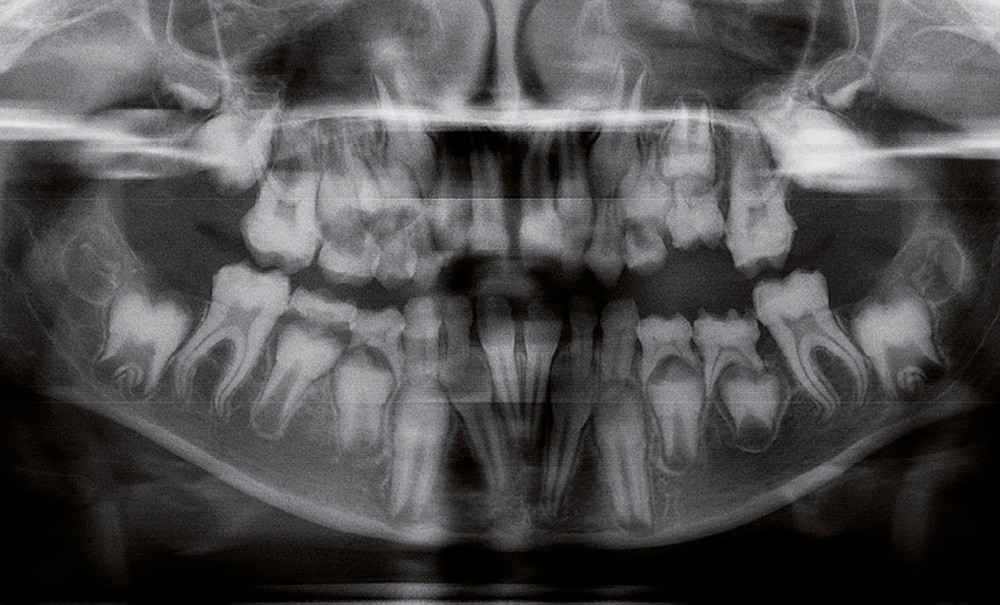

Il existe des anomalies dentaires (tabl. I) [1-12], mais aussi occlusales associées aux AI (fig. 1 et 2).

Selon de nombreuses études, l’anomalie occlusale la plus fréquemment retrouvée en association avec les AI est l’infraclusion antérieure, puisqu’elle est retrouvée chez 22 à 64 % des patients présentant cette affection, et encore plus chez les femmes [2,8,13-19]. Cette anomalie touche tous les types d’AI mais à des degrés très divers. Son incidence semble élevée dans les formes hypominéralisées, moindre dans les formes hypoplasiques et nettement moindre dans les formes hypomatures [8,17,18]. La sévérité de l’atteinte amélaire ne semble pas corrélée avec la présence ou l’intensité de cette malocclusion [17].

En 1982, Rowley et al. [18] ont montré que 44 % des patients atteints d’AI dans leur échantillon, présentaient un angle plan maxillaire (épine nasale antérieure – épine nasale postérieure) /plan mandibulaire (point gonion – point menton) supérieur à 34°, alors que la norme…